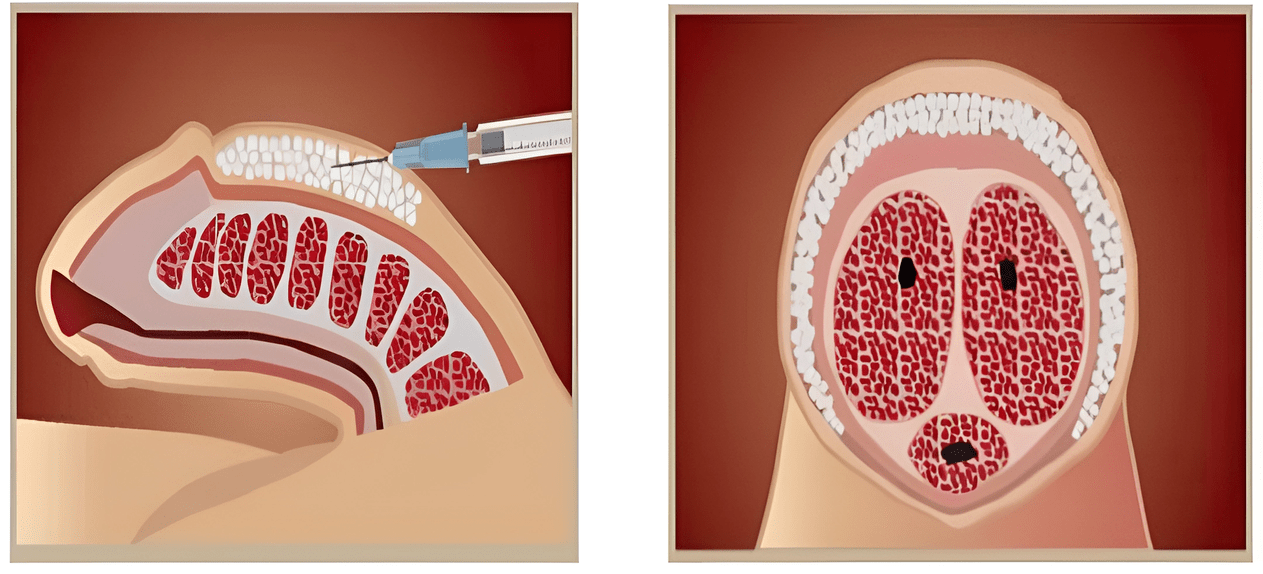

Methods of administration

There are several methods of inserting the filler into the head of the penis. The doctor chooses the technique according to the indications. More often, several methods are combined to improve the aesthetics of the head of the penis:

- Fan method— Hyaluronate is injected with a thin needle in different directions through a fan-type puncture.

- Point method- the injection is performed in a limited part of the penis to eliminate irregularities or deformations.

- Outline presentationThe filler is applied along the crown of the head, after which the contour becomes voluminous and more pronounced.

What results can you expect after the injections?

After inserting the filler into the shaft, its circumference increases by 1-2 cm, and the procedure on the glans not only improves aesthetic qualities, but also lengthens the penis by 3-5 cm. Once under the skin, hyaluronate is distributed evenly. softens the skin and mucous membrane, improving the appearance of the penis. Administration of the gel helps to increase the relief of the crown of the head, its width, highlight the frenulum, makes it more convex, changes the shape and volume of the head.